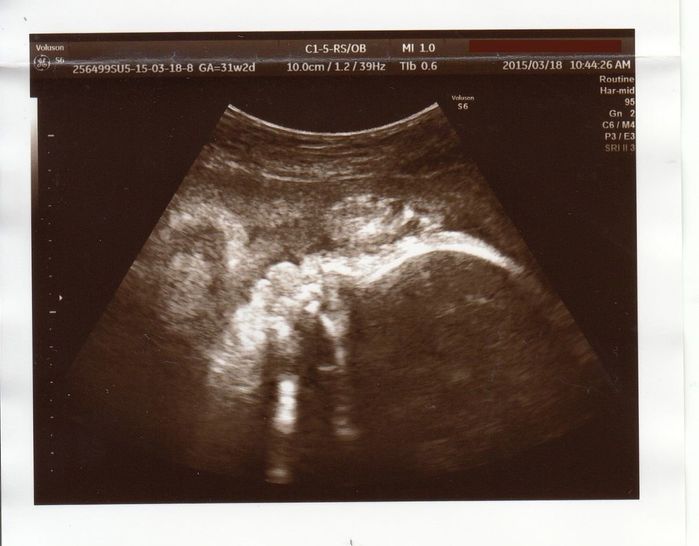

赤ちゃんの体重が思うように増えない - 妊娠31週目のエコー写真

エコーは顔のアップです。右側の曲線が頭です。赤ちゃんの体重が増えず、このままだと保育器のある病院に転院する可能性があると言われてしまいました。どうやったら赤ちゃんの体重が増えるかママ友に相談して、食事の量を増やしたり、なるべく寝て過ごしたり、自分なりにいろいろやってみました。